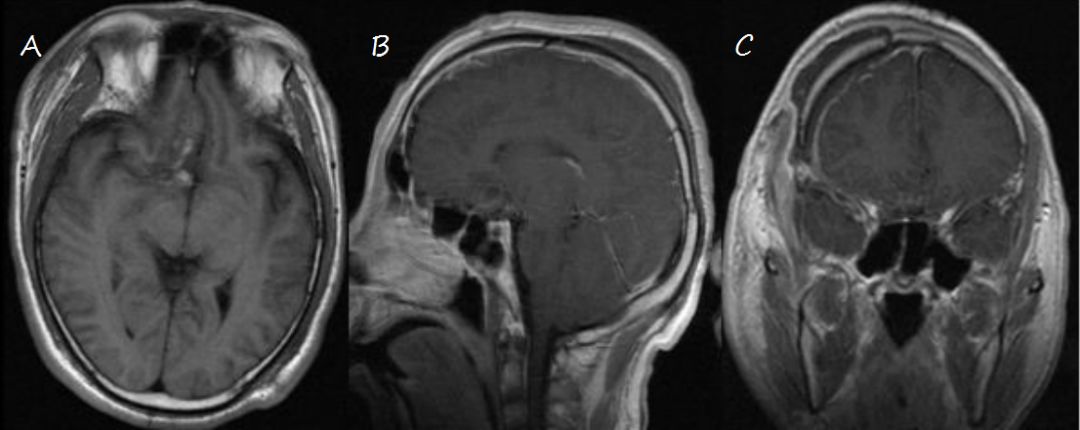

术后患者恢复可,除右侧嗅觉丧失,未遗留其他功能障碍。复查MR提示肿瘤全切(图3)。

图3. 术后复查头颅MRI,示肿瘤全切。